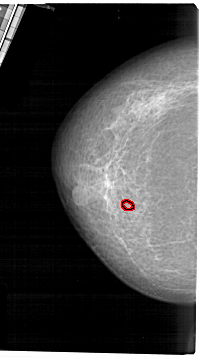

A_1637_1.LEFT_CC

LEFT_CC LINES 5371 PIXELS_PER_LINE 2971 BITS_PER_PIXEL 12 RESOLUTION 43.5 OVERLAY

FILE: A_1637_1.LEFT_CC.OVERLAY

TOTAL_ABNORMALITIES 1

ABNORMALITY 1

LESION_TYPE CALCIFICATION TYPE PLEOMORPHIC DISTRIBUTION CLUSTERED

ASSESSMENT 4

SUBTLETY 1

PATHOLOGY MALIGNANT

TOTAL_OUTLINES 1

BOUNDARY